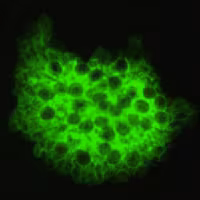

Indirect immunofluorescence using monoclonal antibodies against Pneumocystis jirovecii.

The specific diagnosis is based on identification of P. jirovecii in bronchopulmonary secretions obtained as induced sputum or bronchoalveolar lavage (BAL) material. In situations where these two techniques cannot be used, transbronchial biopsy or open lung biopsy may prove necessary. Microscopic identification of P. jiroveci trophozoites and cysts is performed with stains that demonstrate either the nuclei of trophozoites and intracystic stages (such as Giemsa) or the cyst walls (such as the silver stains). In addition, immunofluorescence microscopy using monoclonal antibodies can identify the organisms with higher sensitivity than conventional microscopy.